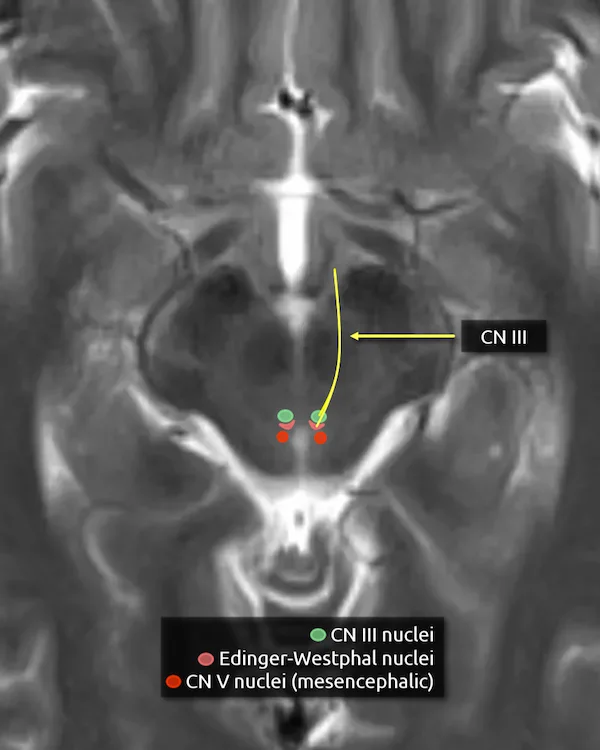

7. Oculomotor nucleus (CN III)

The oculomotor nucleus is located in the upper midbrain posterior to the red nuclei anterior to the cerebral aqueduct. It is one of two nuclei that contributes to the oculomotor nerve. It provides efferent somatic motor fibers.

Lesions involving the oculomotor nucleus are rare but may cause a specific syndrome with bilateral deficits from a unilateral lesion. A single subnucleus spans the midline and supplies the bilateral levator palpebrae muscles, responsible for elevating the eyelids. Additionally, the subnucleus that supplies the superior rectus crosses the midline and supplies both muscles. As a result, nuclear CN III palsy may present with bilateral ptosis and weakness of the bilateral superior rectus muscles. A lesion of solely the nerve fascicle should not cause these symptoms.

8. Edinger-Westphal nucleus

The Edinger-Westphal nucleus is located immediately posterior to the oculomotor nucleus and is the second nucleus that contributes to the oculomotor nerve. It provides parasympathetic motor fibers.

9. Oculomotor nerve (CN III)

The oculomotor nerve exits the brainstem medially after coursing through portions of the red nucleus and substantia nigra. The nerve courses slightly inferior to the axial diagrammatic depiction below, traveling just underneath the mamillary bodies.

Somatic motor innervation:

a. Extraocular muscles (besides the superior oblique and lateral rectus)

b. Levator palpebrae superioris (responsible for elevation of the eyelid)

Parasympathetic motor innervation:

a. Sphincter pupillae muscle (responsible for pupillary constriction)

b. Ciliary body (responsible for light accommodation)

CN III palsy causes the ipsilateral eye to rest in a "down-and-out" position due to unopposed action of the lateral rectus and superior oblique muscles, which are innervated by CN VI and CN IV, respectively. There may also be a unilateral ptosis. The CN III parasympathetic fibers are located on the periphery of the nerve. Because of this, CN III palsy due to compression, e.g., by an aneurysm or a mass, causes a dilated nonreactive pupil. Pupil-sparing CN III palsy is more likely to be due to a medical cause, such as diabetic or hypertensive microangiopathy.